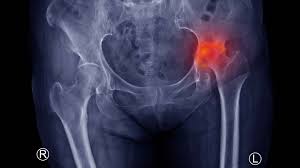

Avascular necrosis (AVN) is a serious condition that occurs when blood supply to a bone is disrupted, leading to bone death and joint damage. In Gadchiroli, patients with persistent hip or knee pain often seek AVN treatment to prevent severe disability and improve mobility. Early intervention is critical, as untreated AVN can progress rapidly, causing joint collapse and chronic pain. Therefore, consulting an experienced orthopedic specialist ensures timely diagnosis, effective treatment, and long-term joint preservation.

Varunam Hospital in Gadchiroli provides comprehensive AVN diagnosis using advanced imaging technologies such as X-rays, MRI, and CT scans. These tools allow orthopedic specialists to detect bone damage in its early stages. Under the clinical leadership of Dr. Utsav Agrawal, Varunam Hospital evaluates each patient thoroughly to determine the extent of AVN and develop personalized treatment strategies. As a result, patients in Gadchiroli can receive accurate diagnosis and early intervention, reducing the risk of joint collapse.

When AVN progresses or non-surgical treatments are insufficient, surgical intervention becomes necessary. Procedures may include core decompression, bone grafting, or total joint replacement, depending on the severity and location of bone damage. Under the supervision of Dr. Utsav Agrawal, Varunam Hospital performs surgeries with precision, following modern protocols to ensure optimal outcomes. Moreover, advanced surgical techniques minimize recovery time, reduce complications, and restore joint function for Gadchiroli patients.